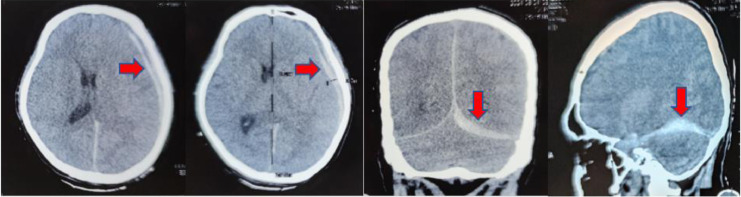

Laboratory results showed hypercoagulopathy with a D-dimer value of 4020. Noncontrast head computed tomography (CT) scan revealed subdural hematoma in the left hemisphere region, cerebral falx, and left cerebellar tentorium. The maximum hematomal thickness of 1 cm, causing a 0.4 cm midline shift, brain edema. No fracture line was seen, subarachnoid or intraparenchymal hemorrhage (Fig. 1).

Fig. 1.

A left-sided acute subdural hematoma (arrow) with midline shift is visible on computed tomography scans, but there is no subarachnoid hemorrhage.